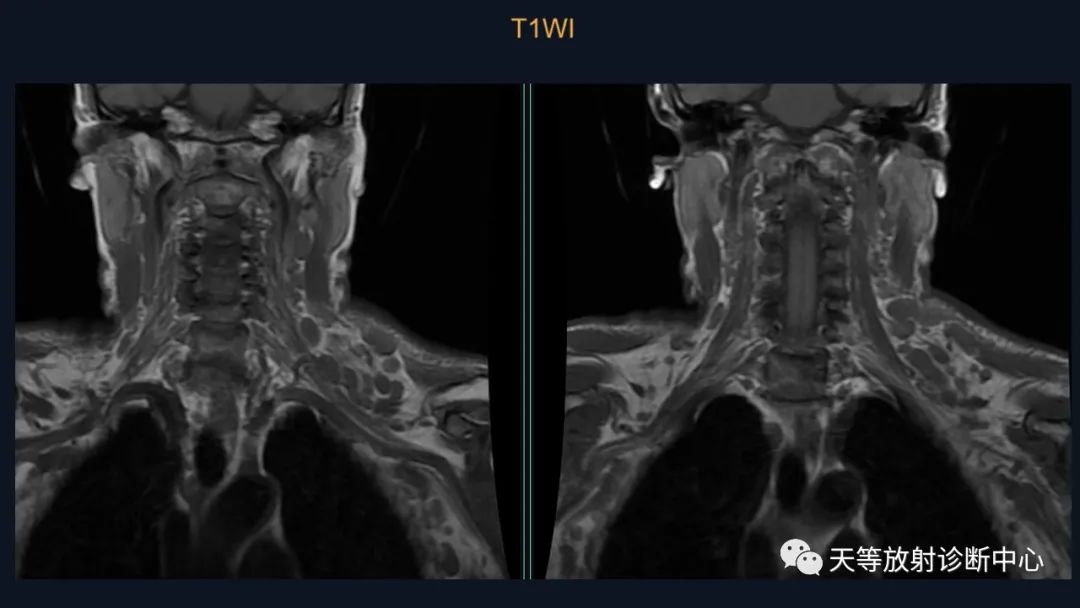

结合颈部、胸廓入口区及腋窝多发淋巴结肿大并相互融合。

综合考虑淋巴瘤